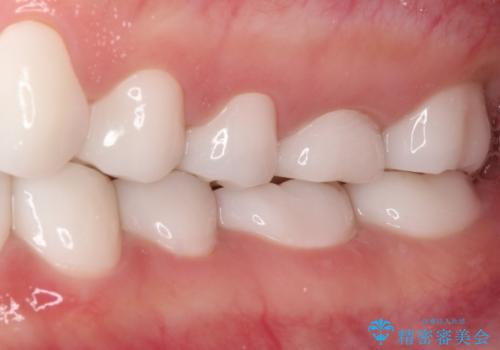

- 奥歯の銀歯をセラミックにしたいとのことで来院された患者様です。

当初は奥歯のみの治療をご希望でしたが、話を進めていくうちに、軽度ではあるものの、幼少期の薬の影響で歯が変色していることがコンプレックスであるということが分かりました。

長年歯の色が塞ぎ込んでいた部分があるとのことで、これを機会に全ての歯を真っ白にするために、オールセラミッククラウンにて補綴治療を行うこととしました。

より白さが目立つように、自然な仕上がりではなく、作り物の雰囲気があるフルジルコニアクラウンにて補綴治療を行いました。